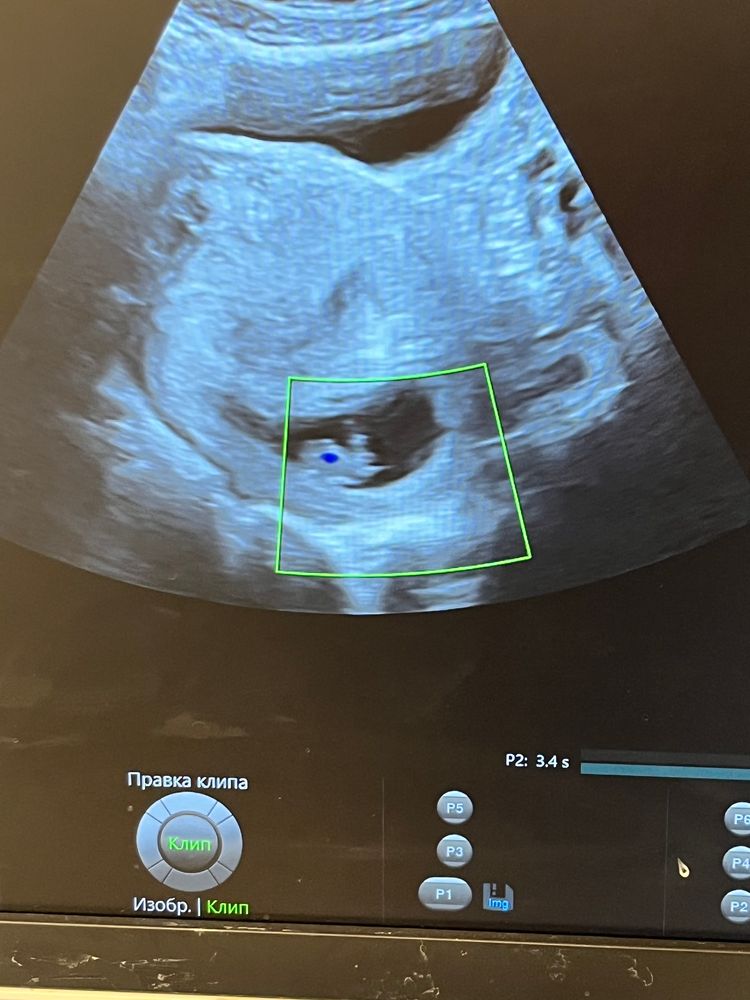

Беременность 9 недель

Беременность- 1 триместр ( только до 10 недель)